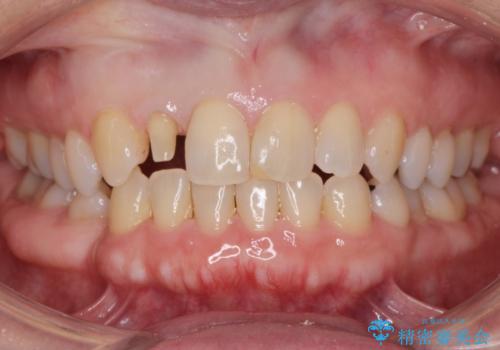

矮小(わいしょう)歯の形をセラミックで自然に 50代女性

- 右上の2番目の前歯がとがった形をしていたため、セラミックで形を整えています。

短くてとがった歯の形が反対側と同じ形となり、左右対称となり、ずいぶん自然な印象になりました。

特に前歯は左右非対象な形のものがありますと、どうしても他人はそこに目が行ってしまい目立ちます。もう八重歯がかわいいという時代は終わったのではないでしょうか。